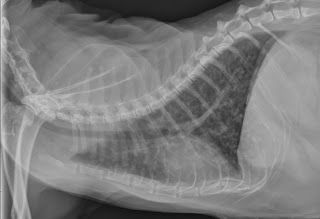

Les radiographies thoraciques peuvent être assez caractéristiques d'une atteinte bronchique mais peuvent aussi être complètement normale chez un chat asthmatique.

Elles permettent néanmoins d'écarter une tumeur, un épanchement pleural ou une infection.